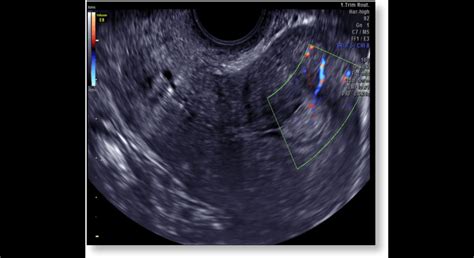

V neskorších fázach tehotenstva sa vykonávajú podrobnejšie ultrazvukové vyšetrenia na posúdenie polohy a veľkosti plodu, stavu placenty a množstva plodovej vody. Taktiež sa meria dĺžka krčka maternice, najmä pri riziku predčasného pôrodu.